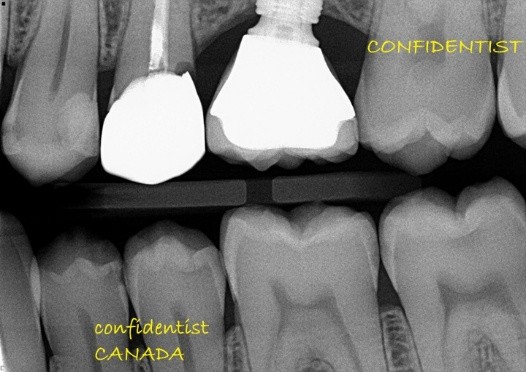

There is radiographic evidence of

Regarding tooth 4.6, there is evidence of